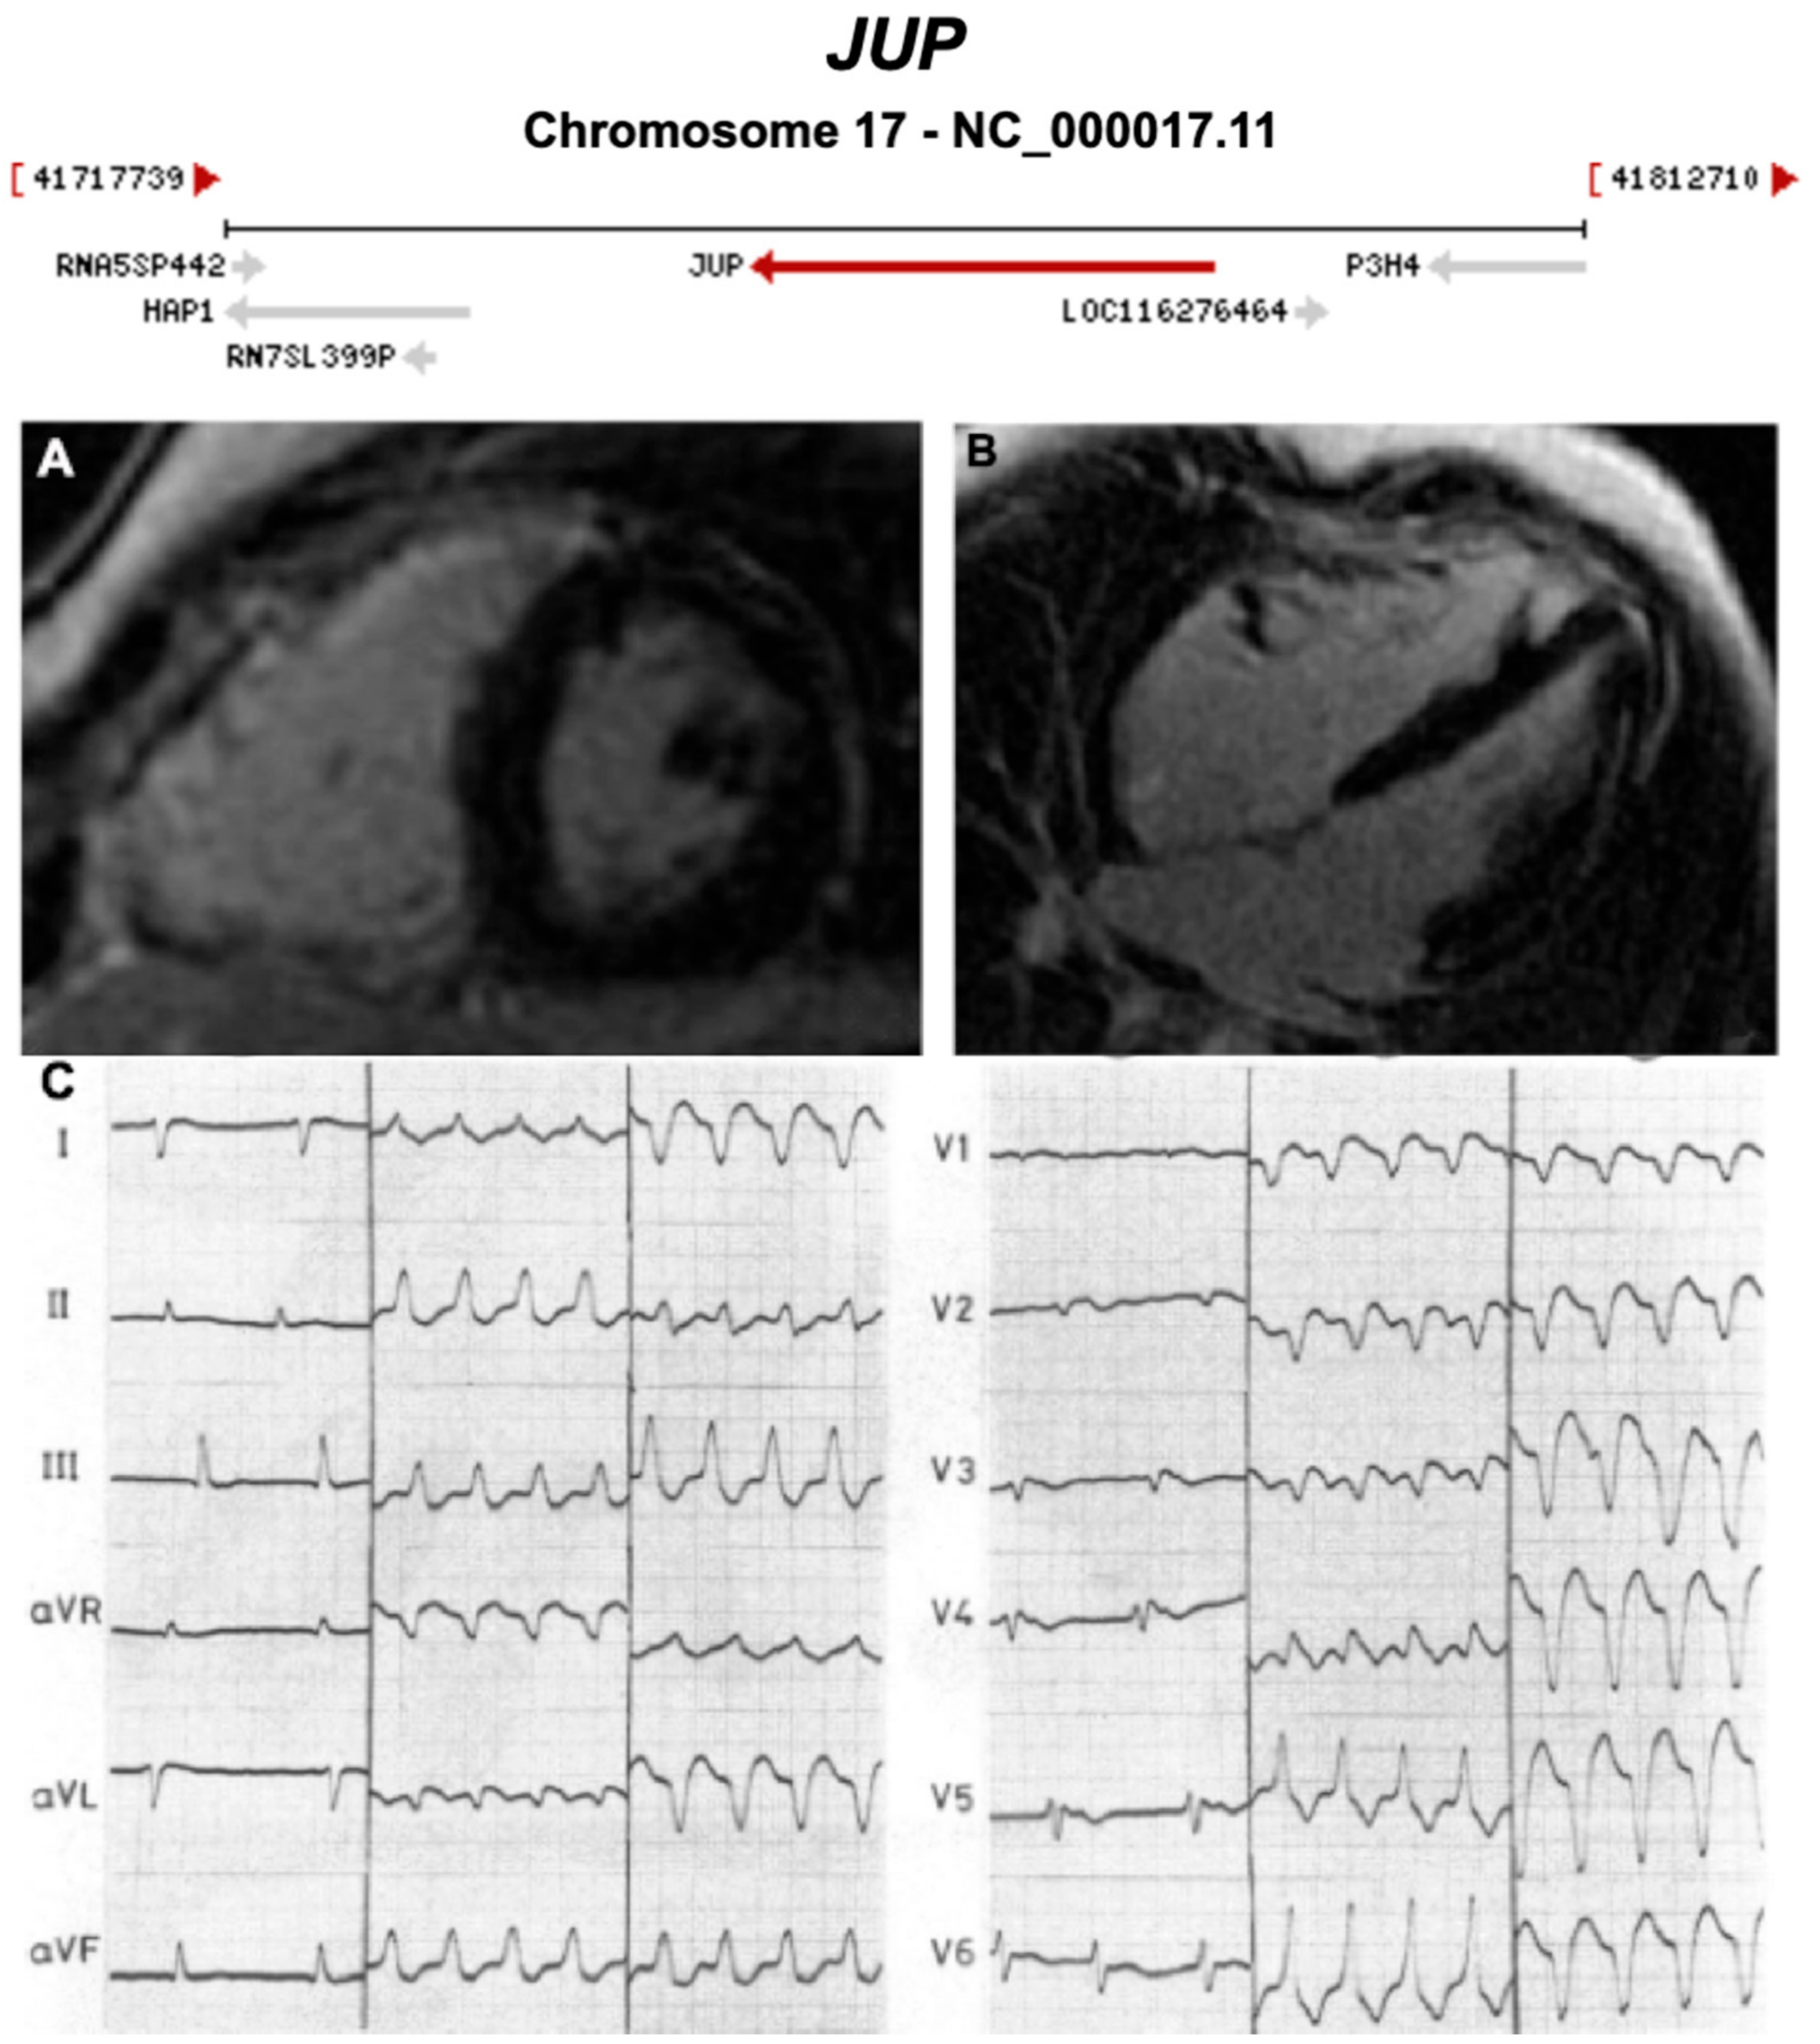

| JUP | Desmosome | 0–1% | AD and AR | RV, BIV | ARVC12 | 17q21.2; 19 | Cardiocutaneous syndrome AR (Naxos) | Definitive for ARVC |